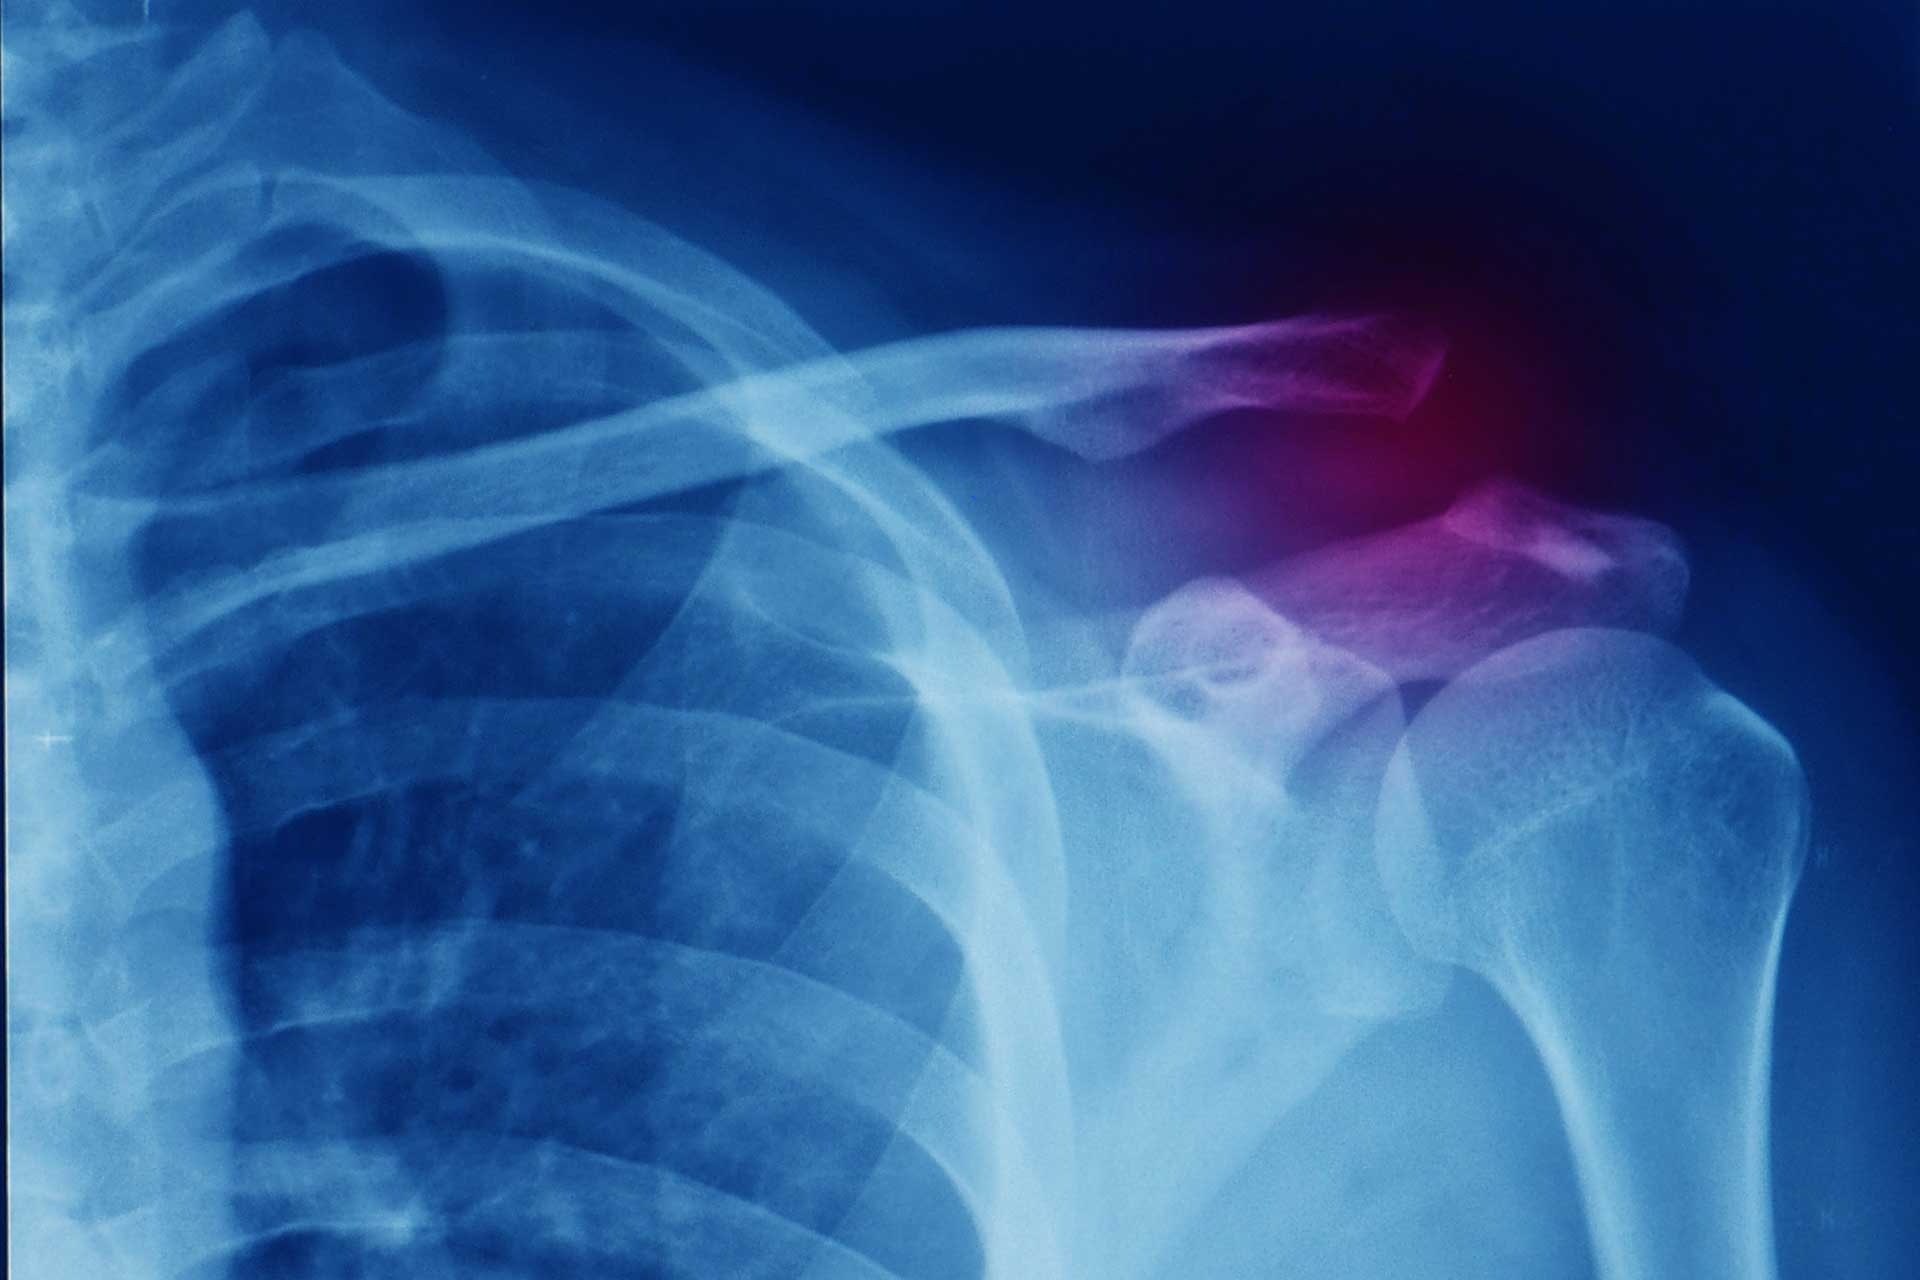

Voici un exercice simple sans matériel qui permet de solliciter le plan musculaire postérieur des épaules. Réalisé de façon statique ou dynamique il peut être utile pour les personnes qui présentent des douleurs d’épaules mais aussi en prévention de leur apparition.